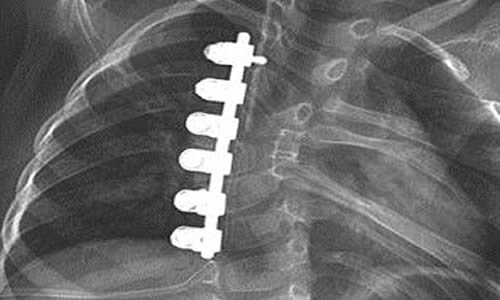

Adölesan İdiopatik Skolyoz tedavisinde korse tedavisinin yeri cerrahi tedavi yöntemlerinin gelişmesi ile azalmaktadır, ancak yine de uygun hastalarda tercih edilen bir tedavi yöntemidir. Korse tedavisi, oluşan eğriliği mekanik olarak temas noktalarından orta hatta iten ve aynı zamanda omurgaya (traksiyon) asılma gücünü uygulayan bir prensiple çalışır. Bu temas noktaları leğen kemiği, koltuk altı, göğüs kemiği (sternum) ve eğriliklerin en çıkıntılı yerleridir. Eğriliğin yerleşim yeri boyna yakınsa kafayı da içeren ilave temas noktaları eklenir.